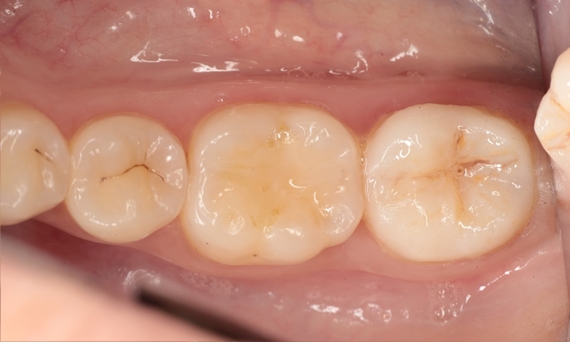

Before: Insufficient fillings in the second quadrant. The restorations were about 15 years old.

After: Chairside-fabricated crowns made from CEREC Tessera (teeth 26/27). Inlays for teeth 24 and 25 made of composite blocks.